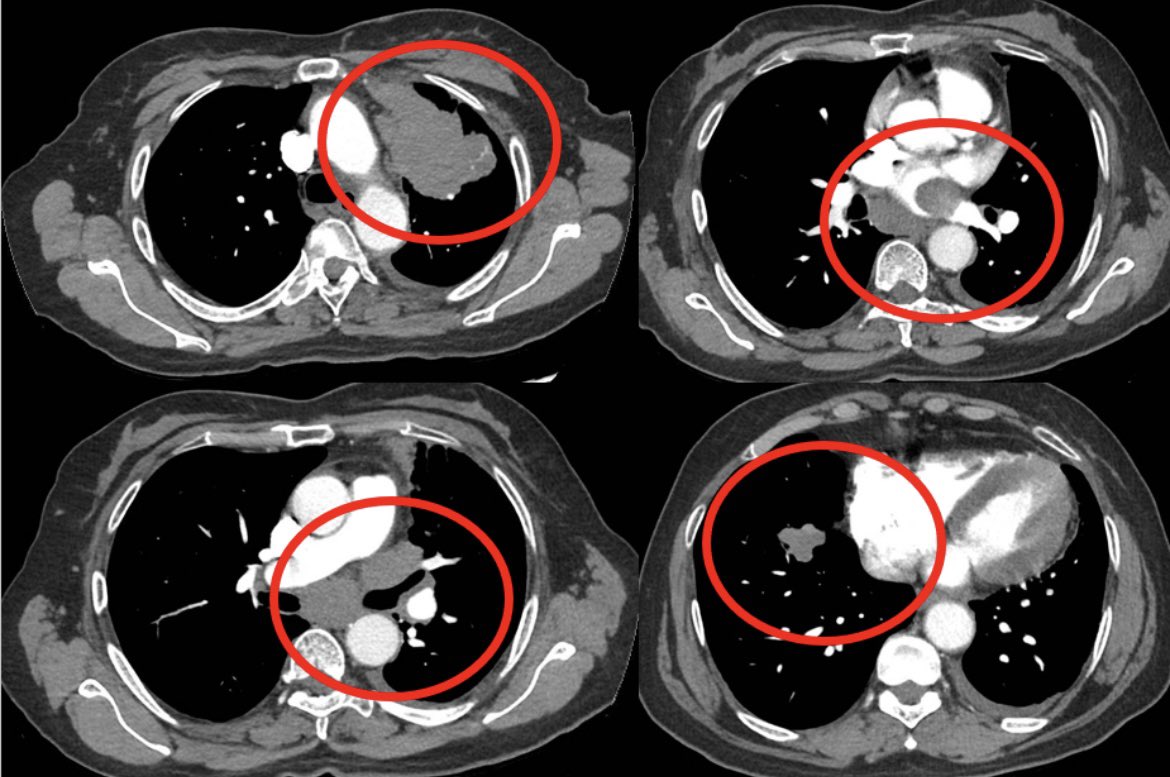

The patient with a broken heart.

Pt in mid 60s with past smoking history presented with chest discomfort and dyspnea

Evaluation with CTA showed no PE but demonstrated a very large LUL mass with direct extension into mediastinum and L atrium and additional R sided lung lesions c/w st4 disease

Cardiac MR and ECHO confirm a mobile mass in L atrium contiguous w LUL mass

Path shows lung adenoca, PD-L1 TPS score >90%, ctDNA+ for K-Ras G12C

Tumor board review: surg/IR interventions not feasible, XRT likely not safe/effective, chemo - concern as to heme tox w heart invaded

Pt started on single agent IO

Patient has tolerated single agent IO well with limited eczematous derm AEs

Early ctDNA repeat showed clearance of ctDNA

Repeat imaging after 4 cycles demonstrated dramatic response to single agent IO w complete resolution of atrial/cardiac findings!

Guess it is good to have those hard-working T cells in circulation…

Heartfelt thanks to immunotherapy!!!